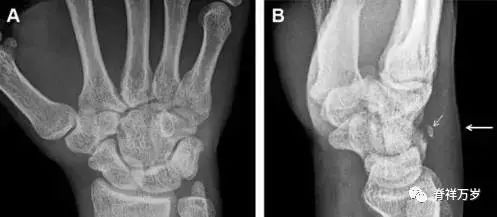

30.桡骨远端骨折

常规进行前后位、侧位、斜位 X 线检查,对于大多数桡骨远端骨折来说不容易漏诊;但是对于无移位的骨折,特别是桡骨茎突骨折,容易漏诊。桡骨茎突骨折是一斜行的骨折,常累及关节面,常发生于轴向应力或直接打击。

图 1 57 岁女性,摔倒后手掌撑地,桡骨茎突压痛。(A~C)前后位、斜位、侧位片示软组织肿胀(*)和发丝样骨折(白色箭头);(D~F)2 周后,前后位、斜位、侧位片示骨折线显明,由于新骨痂沉积而呈现透亮线与硬化线并存;(G~I)另一患者,桡骨茎突骨折在前后位及侧位片上显示不明显,而在斜位片显示更清楚。